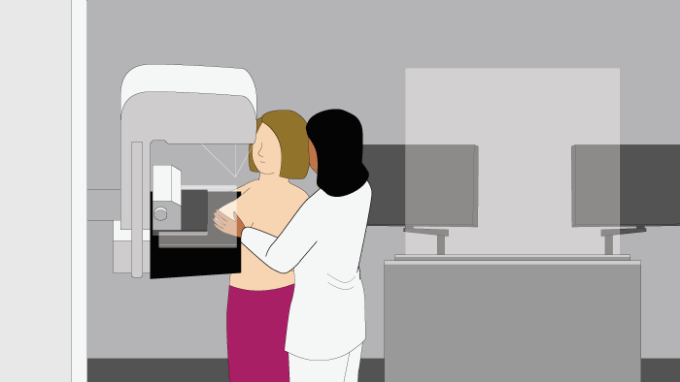

Het viel uiteindelijk mee! Het is zeker niet prettig maar echt super pijnlijk was het nou ook weer niet: Je staat ongemakkelijk. Je borst wordt op zo’n ‘tafeltje’ gekleid en dan komt de plexiglas plaat erop. Handmatig geeft de verpleegkundige nog een kleine extra draai aan de plaat en dan gaat de ‘kopieer-machine’ er bovenlangs.

In totaal gebeurt dat 4x, elke borst in 2 standen. Daarna mag je door naar de volgende ronde voor de echo. De radiologe met koude vingers, smeert de op lichaamstemperatuur gebrachte gel op de borst want anders zou je er maar van schrikken (nee, die koude vingers waren prima😉). De ene na de andere zwarte plekje wordt zwijgend aangeklikt en opgemeten op het scherm…

[…] maar gelukkig bleek het een onschuldige cyste (een met vocht gevulde holte). Ik schreef er een blog over en beschreef hoe een mammografie nou in zijn werk […]